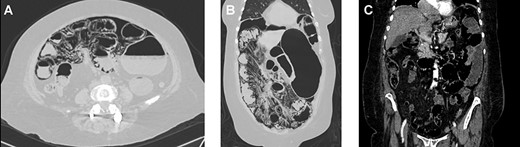

On clinical examination, we encountered a tachycardic (122 bpm) and dehydrated patient. Her capillary refill time was <2 seconds, but her skin was cold and dry to touch. Her abdomen was distended, and pain was found in her lower abdomen with no signs of tenderness. After adequate reanimation, complementary examinations were requested. Blood results detected leukocytosis (13 000 cell/mm3), neutrophilia (83%) and hypokalemia (3.1 mEq/L). Distended loops of the small bowel were observed on the abdominal X-ray. Because of this, a contrast-enhanced abdominal computed tomography (CT) was performed revealing multiple cystic round shapes in the wall of the jejunum and mesentery. Additionally, a bubbly pattern of gas was present across all the length of the small bowel. The rest of the bowel appeared normal with no signs of pneumoperitoneum, pneumobilia, gas in the portal venous system or free liquid (Fig. 1A–C). The patient was admitted to the ward but after 24 hours of close monitoring her pain persisted. A life-threatening condition was suspected, and surgery decided.

(A) Computed tomography (CT), revealing pneumatosis intestinalis on the bowel wall. (B) CT, revealing multiples gas-filled cysts in the bowel and on the mesentery. (C) CT, no evidence of gas in the portal system.